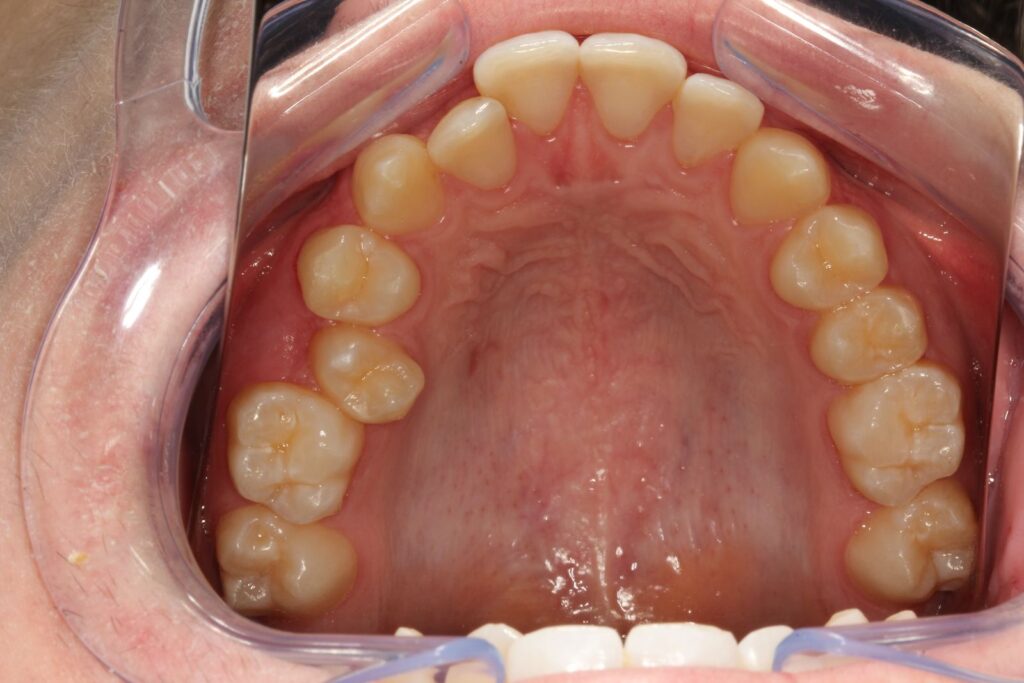

Paciente com tratamento finalizado em 8 meses!

Com disciplina no uso e acompanhamento regular, os resultados costumam aparecer em poucos meses, proporcionando um sorriso alinhado, harmônico e natural.